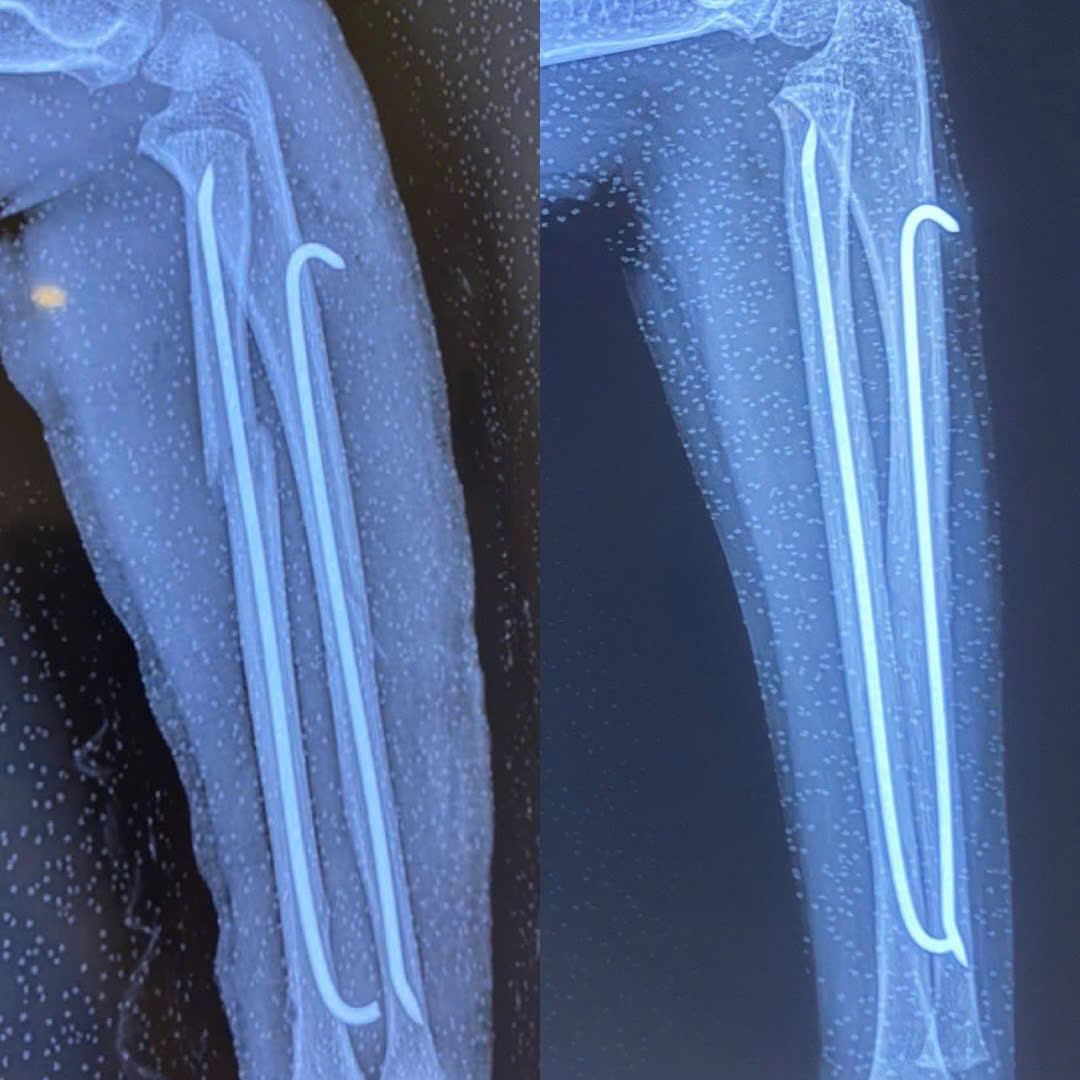

Hình ảnh X-quang sau khi phẫu thuật kết hợp xương (trái) và trước khi tháo phương tiện kết hợp xương (phải)